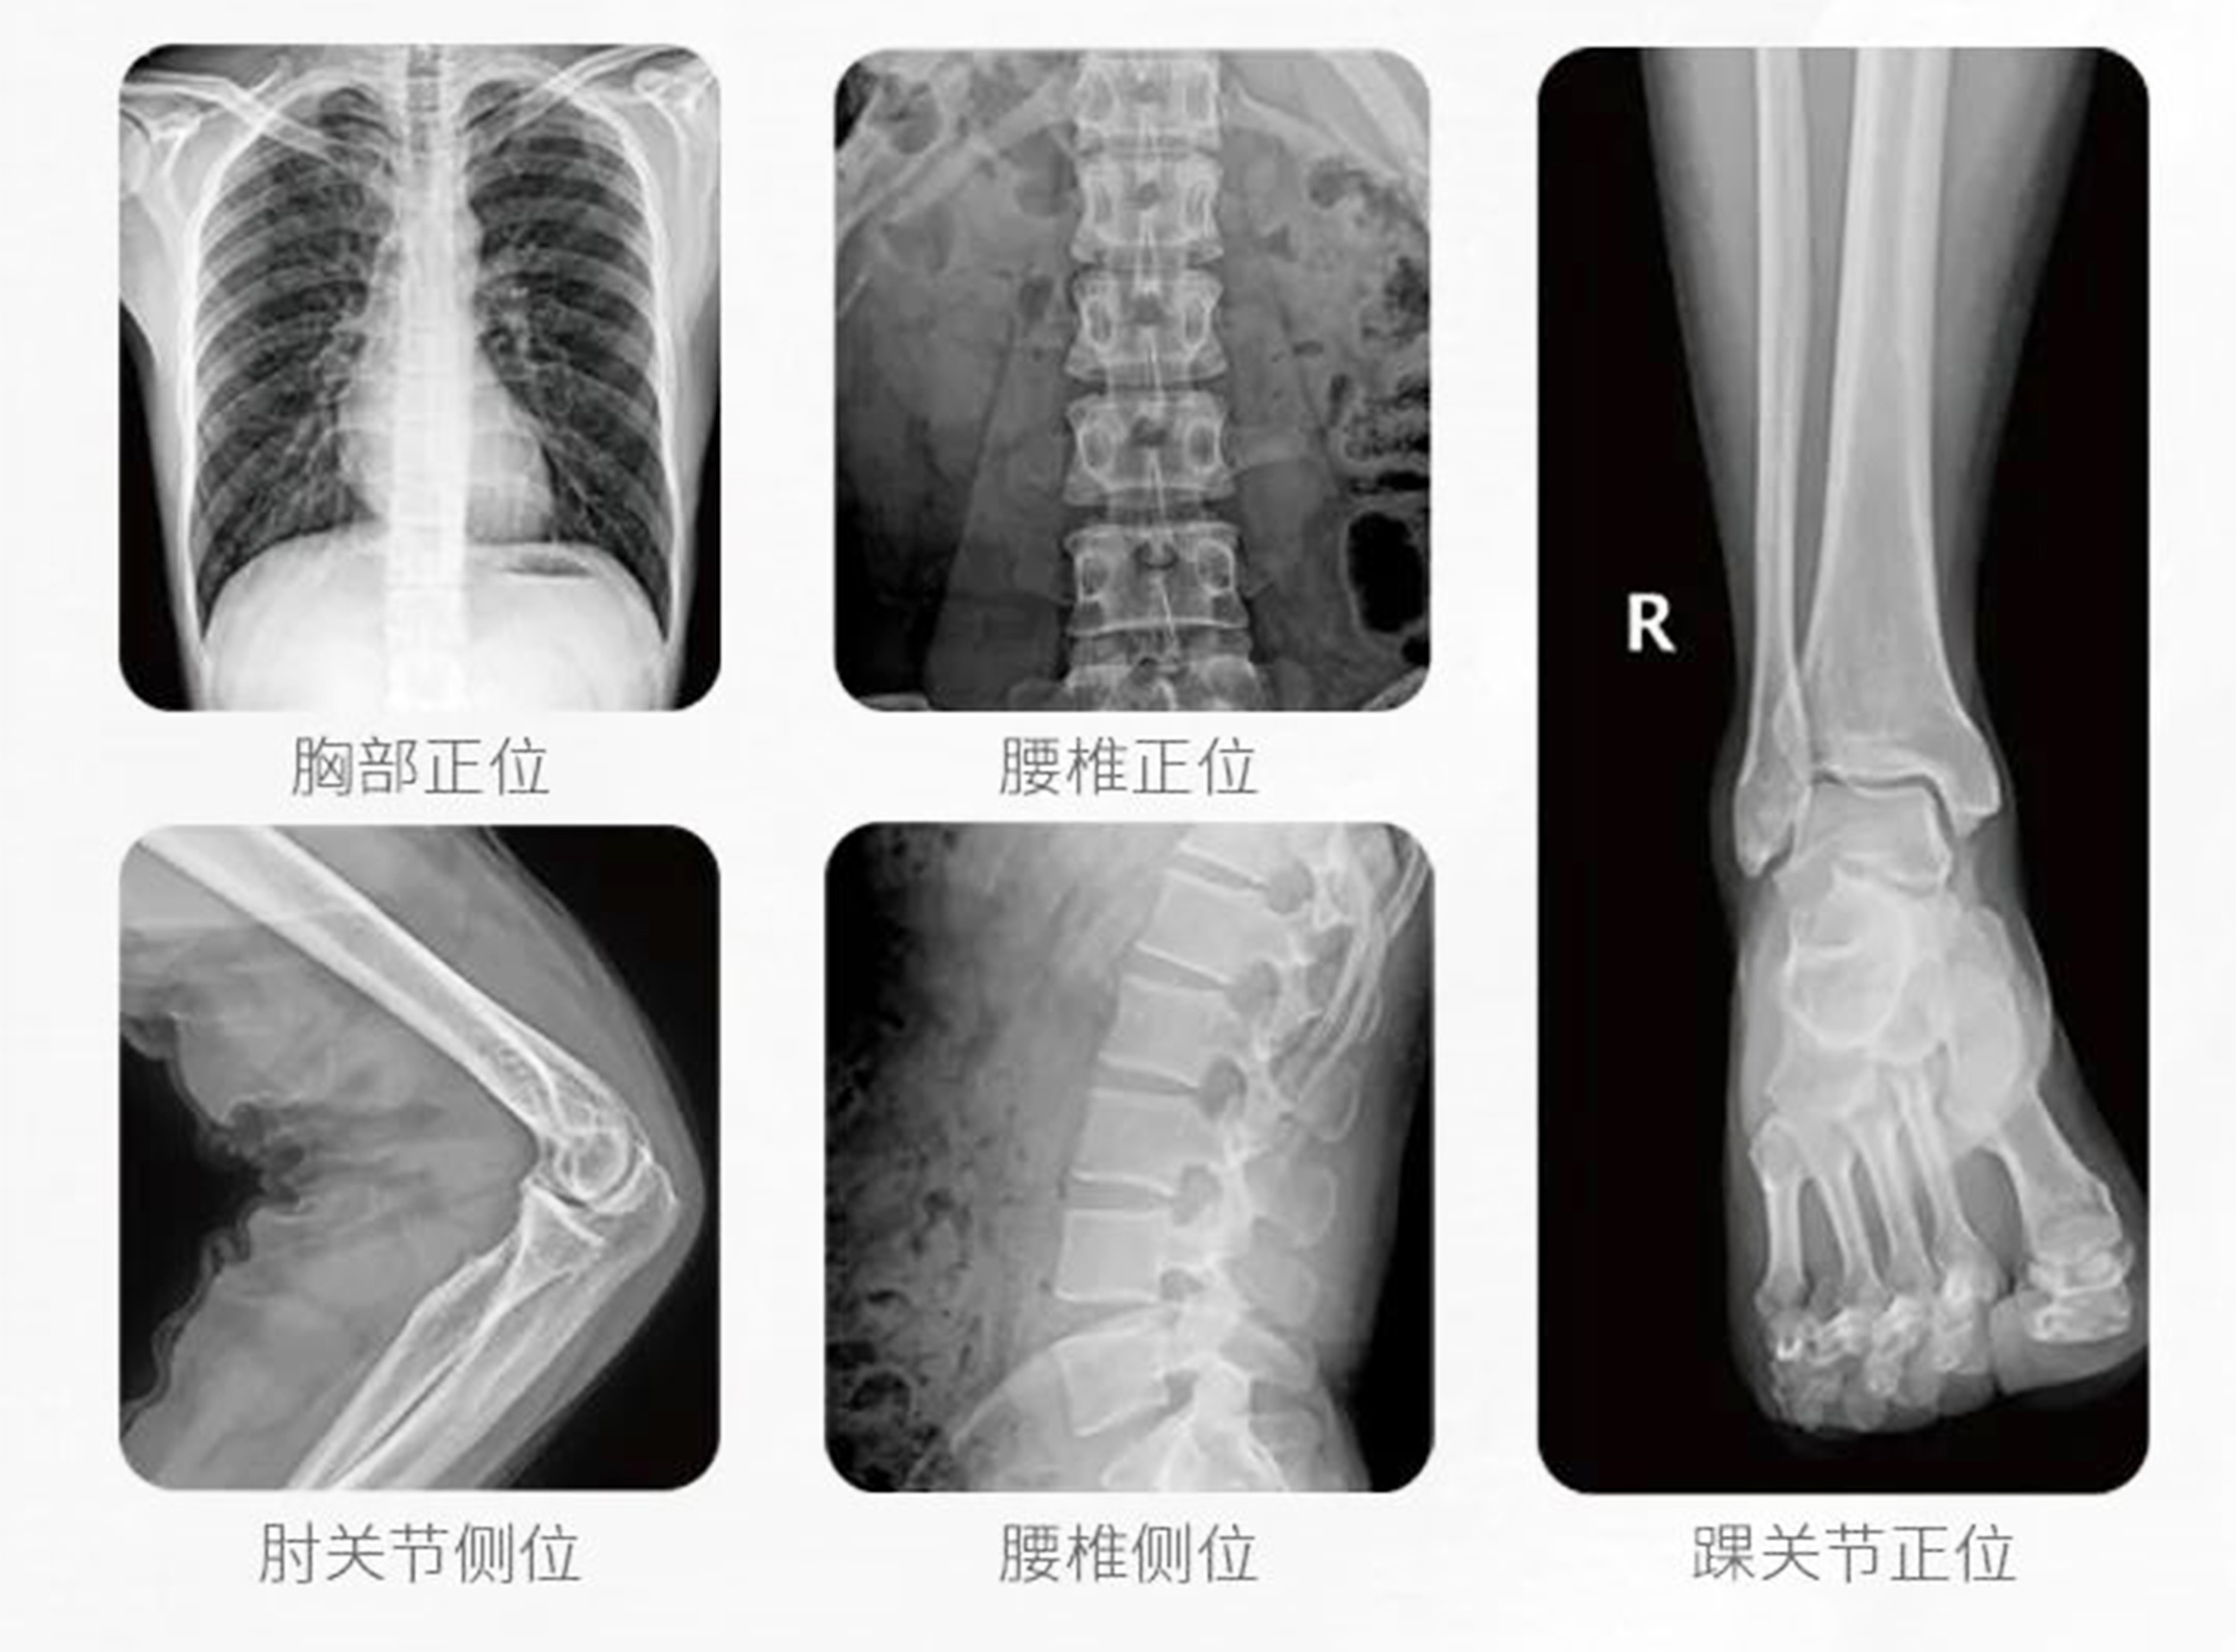

移動式DR是一款什么樣的DR設備?DR設備是數字化直接成像系統的簡稱,與傳統X光成像相比,DR具備圖像更清晰、輻射量更低、檢查速度更快、檢查成功率更高等優點。而移動式DR就是可以移動的DR設備,除具有一般DR的特點之外,還具備普通DR機所不具備的便攜、移動靈活、占地面積小等優勢。

2.快速成像:可以在曝光幾秒鐘后快速獲取攝影圖像并確認,省去了傳統洗片和IP板信息讀取等繁雜程序,圖像可現場處理、實現網絡傳輸、打印。

4.機械運動靈活便捷:可以拍攝全身各個部位,方便醫師從不同角度觀察患部,便于確診。

5.影像清晰:高品質高頻高壓發生器。國際先進的數字平板探測器,確保優質的圖像效果。

普愛醫療移動式DR滿足隔離病房、ICU、急診室、呼吸科及疾控中心的特殊使用,快速完成胸部及全身其它部位的數字化攝影檢查,即拍即得,可做到專機專用,避免交叉感染,對診斷病情不可或缺。如果您想采購這款產品,歡迎咨詢400-025-6366。